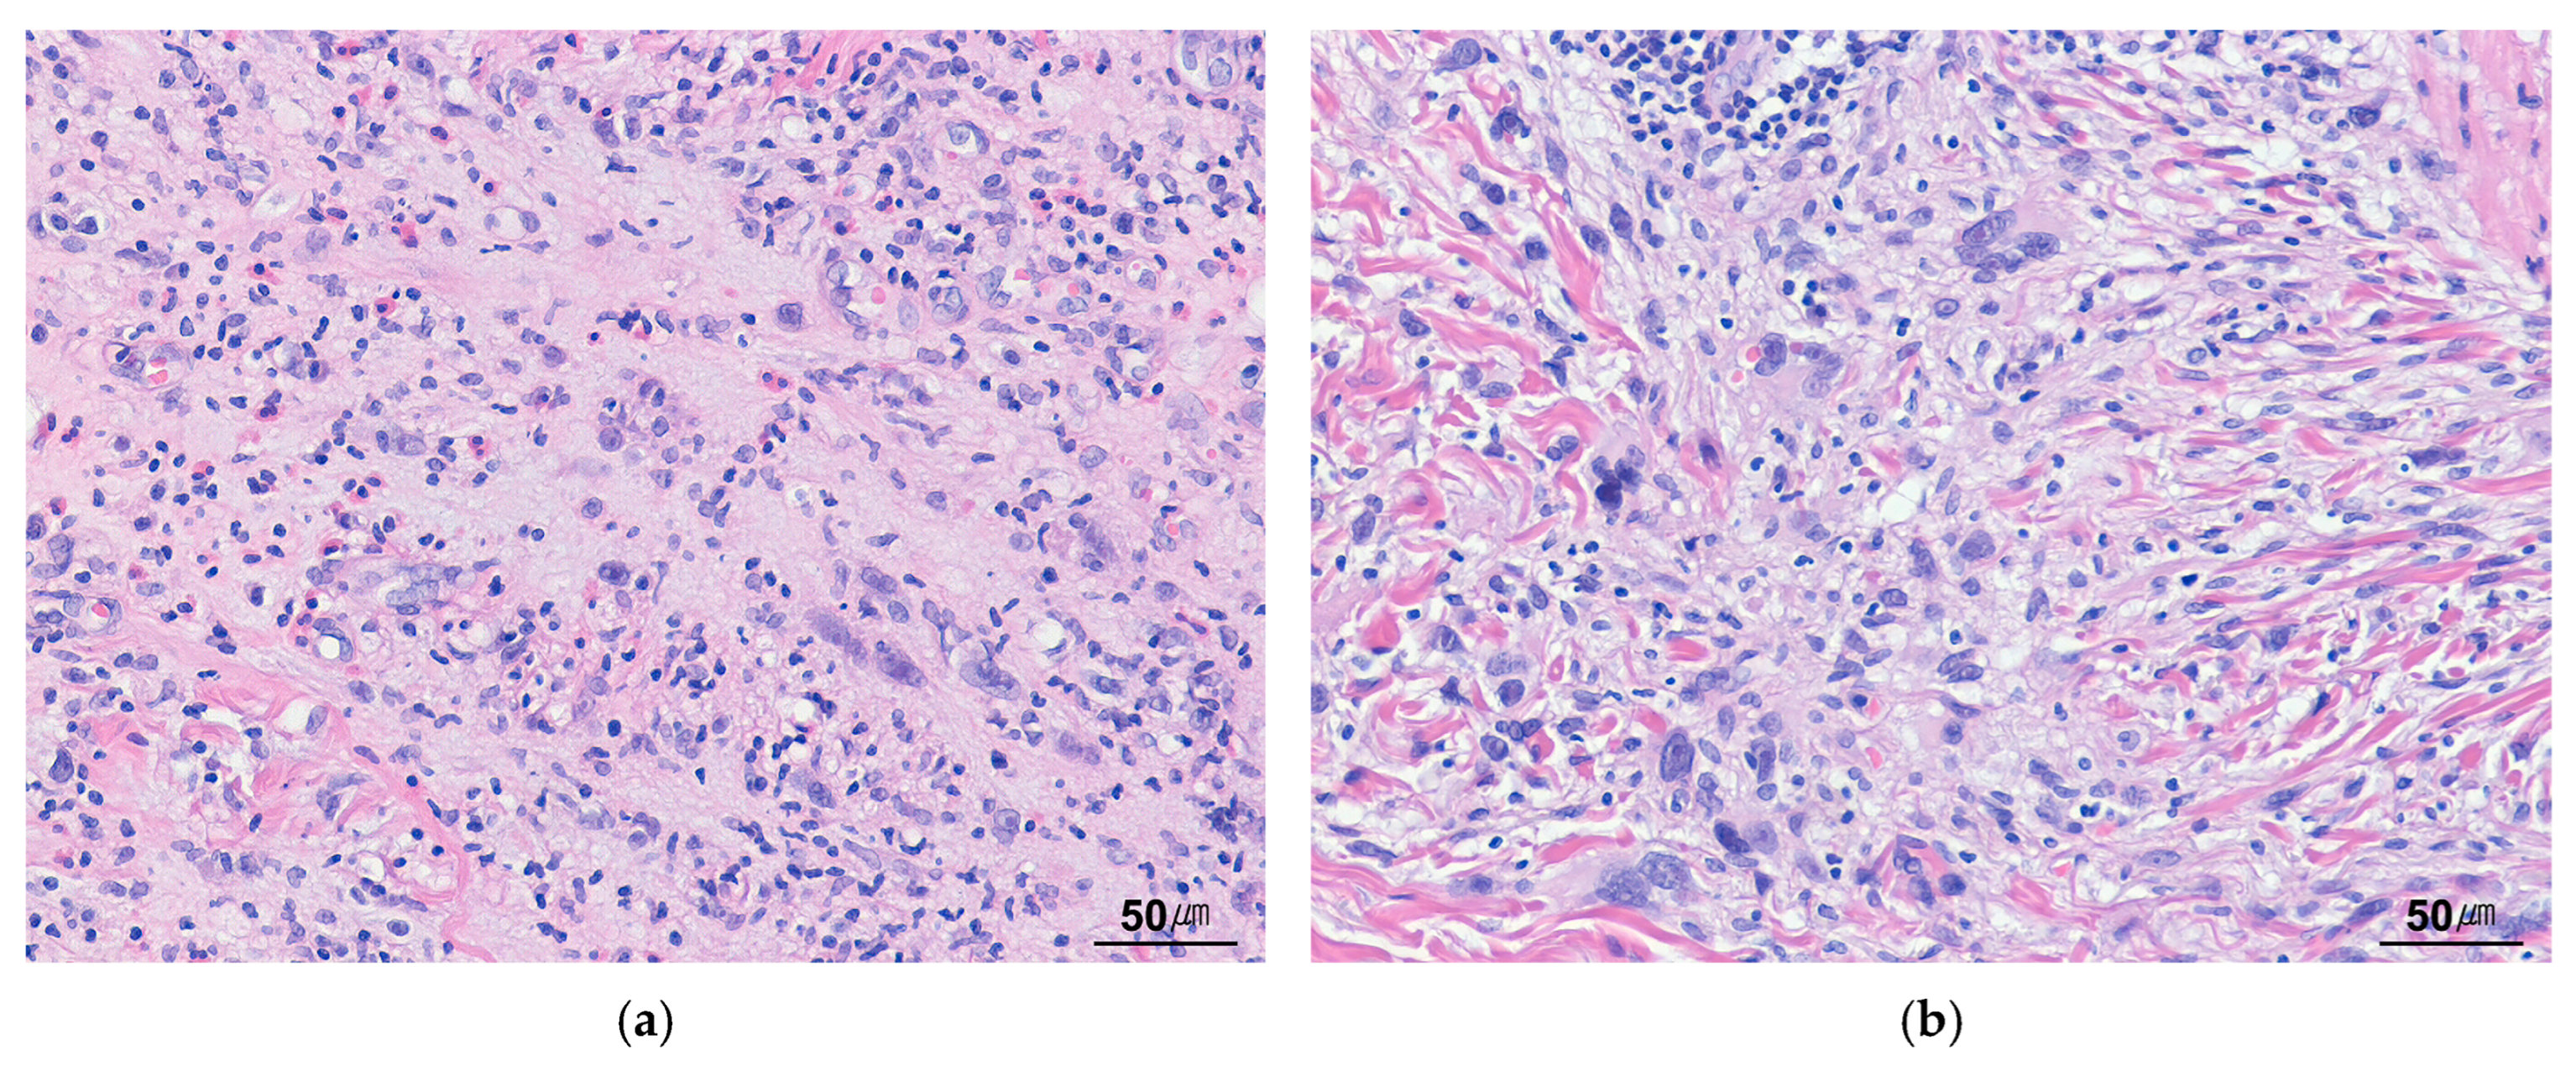

4.2. Histopathology

| Myxoid (a) | Loosely arranged plump or spindled myofibroblasts; edematous myxoid background; abundant blood vessels; infiltrate of plasma cells, lymphocytes, and eosinophils | Inflammatory pseudotumor Inflammatory fibroid polyp Nodular fasciitis Myxoinflammatory fibroblastic sarcoma |

| Hypercellular | Compact spindle cells proliferation in fascicular or storiform patterns; variably myxoid and collagenous stroma; prominent inflammatory infiltrate. | Pseudosarcomatous myofibroblastic proliferation Inflammatory well-differentiated liposarcoma Low-grade myofibroblastic sarcoma Inflammatory leiomyosarcoma Embryonal rhabdomyosarcoma Gastrointestinal stromal tumor Epstein–Barr virus-positive inflammatory follicular dendritic cell sarcoma |